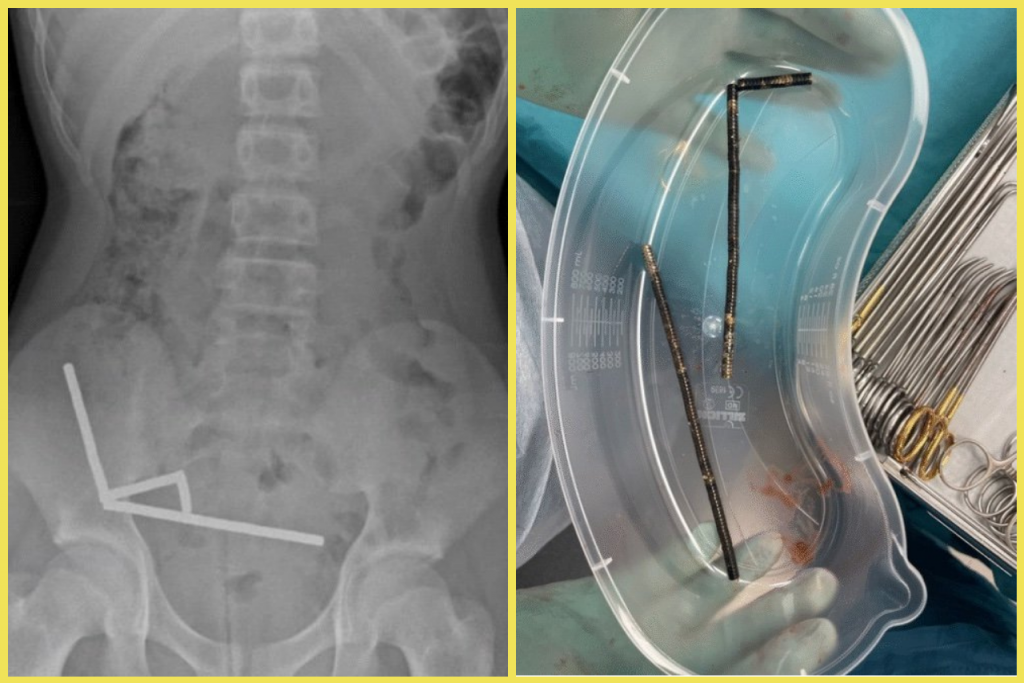

Ako operácia prebiehala a prečo ju na Slovensku vykonali až teraz?

Operácia bola prevedená v troch krokoch. V prvom sme zaviedli elektródy do pravej hemisféry a ovplyvnili tak ľavú stranu tela, v druhom sme to zopakovali aj na ľavej hemisfére. V poslednej fáze ide pacient do celkovej anestézy, kedy elektródy spájame pomocou predlžovacích káblov s generátorom uloženým pod kľúčnou kosťou. Tieto operácie boli realizované na Slovensku aj doteraz, len pri nich pacient musel mať na hlave počas zákroku prifixovaný stereotaktický rám.